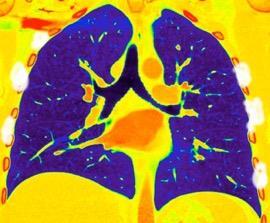

Nódulo en língula.

Cirugía de Ca .de mama hace 23 añosedema de brazo y ganglio en axila. ¡Metástasis!.